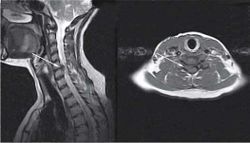

К дистрофическим изменениям позвоночника, определяемым при МРТ, относят снижение интенсивности сигнала от дисков, их выпячивание, формирование протрузий, экструзий и секвестрация, складчатость фиброзного кольца, изменение сигнала от концевых пластинок, «вакуум-феномен», стеноз канала. Под выпячиванием диска понимают циркулярное, симметричное выбухание фиброзного кольца диска за пределы замыкательных пластинок тел прилежащих позвонков. Термин «протрузия» (грыжа пульпозного ядра, пролапс) означает истончение фиброзного кольца с фокальным пролабированием пульпозного ядра за края замыкательных пластинок тел прилежащих позвонков. При протрузии не нарушается целостность задней продольной связки и сохраняются самые наружные волокна фиброзного кольца. Экструзия - пролабирование пульпозного ядра за пределы фиброзного кольца, при этом часть диска, подвергшаяся экструзии, связана с оставшимся пульпозным ядром тонкой ножкой (рис. 12). Протрузии и экструзии по направлению их пролабирования условно подразделяют на передние (расположенные по передней полуокружности тел позвонков, не имеющие большого клинического значения) и задние. Последние можно разделить на латеральные (направленные в сторону межпозвоночного отверстия), парамедианные и срединные (рис. 13). Секвестрация - термин, применяющийся для обозначения формирования свободного фрагмента, полностью утратившего связь с диском.

Методы визуализации с высокой частотой выявляют патологию межпозвонковых дисков (дегидратация, протрузии, экструзии) даже у асимптомных обследованных. Асимптомные протрузии дисков выявляют в 35% случаев в возрастной группе от 25 до 39 лет и в 100% случаев у лиц старше 60 лет. Не выявлено прямой зависимости между размерами центрального канала, протрузией и экструзией дисков и появлением признаков компрессии корешков. Соответственно, интерпретацию данных визуализации необходимо проводить только при сопоставлении с данными неврологического и невроортопедического обследования пациента.

Для исключения стеноза спинномозгового канала необходимо знание его нормальных размеров. Его сагиттальный размер в шейном отделе позвоночника колеблется от 21 мм на уровне CI-СIII до 18 мм на уровне CIV-СVII. При этом переднезадний размер спинного мозга в шейном отделе позвоночника составляет от 7 до 11 мм, занимая до 40% позвоночного канала. При экстензии сагиттальный размер позвоночного канала уменьшается на 2-3 мм, что создает условия для повреждения спинного мозга при гиперэкстензионных травмах у лиц с врожденной или приобретенной узостью позвоночного канала. В поясничном отделе сагиттальный размер позвоночного канала в среднем составляет около 18 мм. Отмечают тенденцию к изменению формы позвоночного канала от LI к LV. Переднезадний размер позвоночного канала в поясничном отделе позвоночника минимален на уровне тел LIII и LIV; это создает условия для более частого формирования на этом уровне поясничного стеноза при дистрофическом изменении позвоночника и дугоотростчатых суставов.